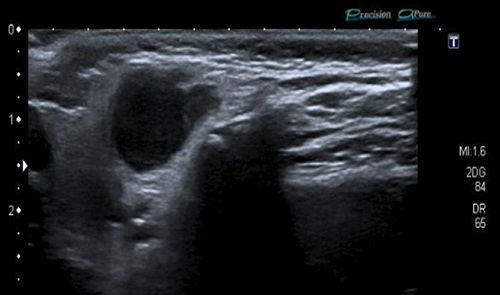

Paciente varón de 23 meses, asintomático, que acude con su madre porque esta detecta tumoración cervical anterior izquierda 24 horas antes. Antecedentes familiares y personales sin interés. Vacunaciones adecuadas para su edad. No alergias conocidas. El paciente presenta muy buen estado general, apirético y con exploración normal salvo adenopatía única de 2,5 x 3 cm en región cervical anterior izquierda, de consistencia no blanda, no adherida a planos profundos, no caliente y con piel suprayacente normal. No lesiones en la piel próxima a la misma. Se inicia tratamiento con amoxicilina-clavulánico. Se reevalúa en 4 días, llamando la atención la persistencia de la adenopatía, lo que contrasta con el buen estado general del niño, que seguía asintomático. Los estudios de hematología, bioquímica, serología de citomegalovirus (CMV), virus de Epstein-Barr (VEB), virus herpes 6 y toxoplasmosis fueron normales o negativos. Prueba de tuberculina a las 48 h: 6 mm de induración, sin haber factores de riesgo de tuberculosis. Radiografía de tórax normal. Con sospecha de adenitis por MNT se deriva a hospital. El estudio ecográfico se informa como: “lesión de 1,7 x 3,5 x 2,3 cm, polilobulada, de ecogenicidad media, con la porción anterior, mal definida, sin aumento de la vascularización en el Doppler. Hay cambios inflamatorios en el tejido celular y la piel cercanas a la lesión (se encuentra a 6 mm de la piel). Resto del cuello con ganglios inespecíficos. Glándula tiroidea sin alteraciones. Los hallazgos son compatibles con adenitis por micobacterias con extensión fuera del ganglio y cambios inflamatorios en piel y tejido celular subcutáneo (posible incipiente fistulización)” (Fig. 1). Por medio de punción-aspiración con aguja fina (PAFF) se consigue material para cultivo que resulta positivo para M. lentiflavum (Fig. 2). Dado el alto grado de resistencia y el riesgo de que la intervención quirúrgica pueda dañar fibras nerviosas de nervio facial se decide, junto con los padres, la actitud de ver evolución espontánea. La adenopatía fistuliza a los 2 meses, quedando una cicatriz residual 2 años y 10 meses después (Fig. 3).

Figura 1. Paciente de 23 meses. Ecografía de nódulo cervical por micobacterias no tuberculosas (M. lentiflavum)